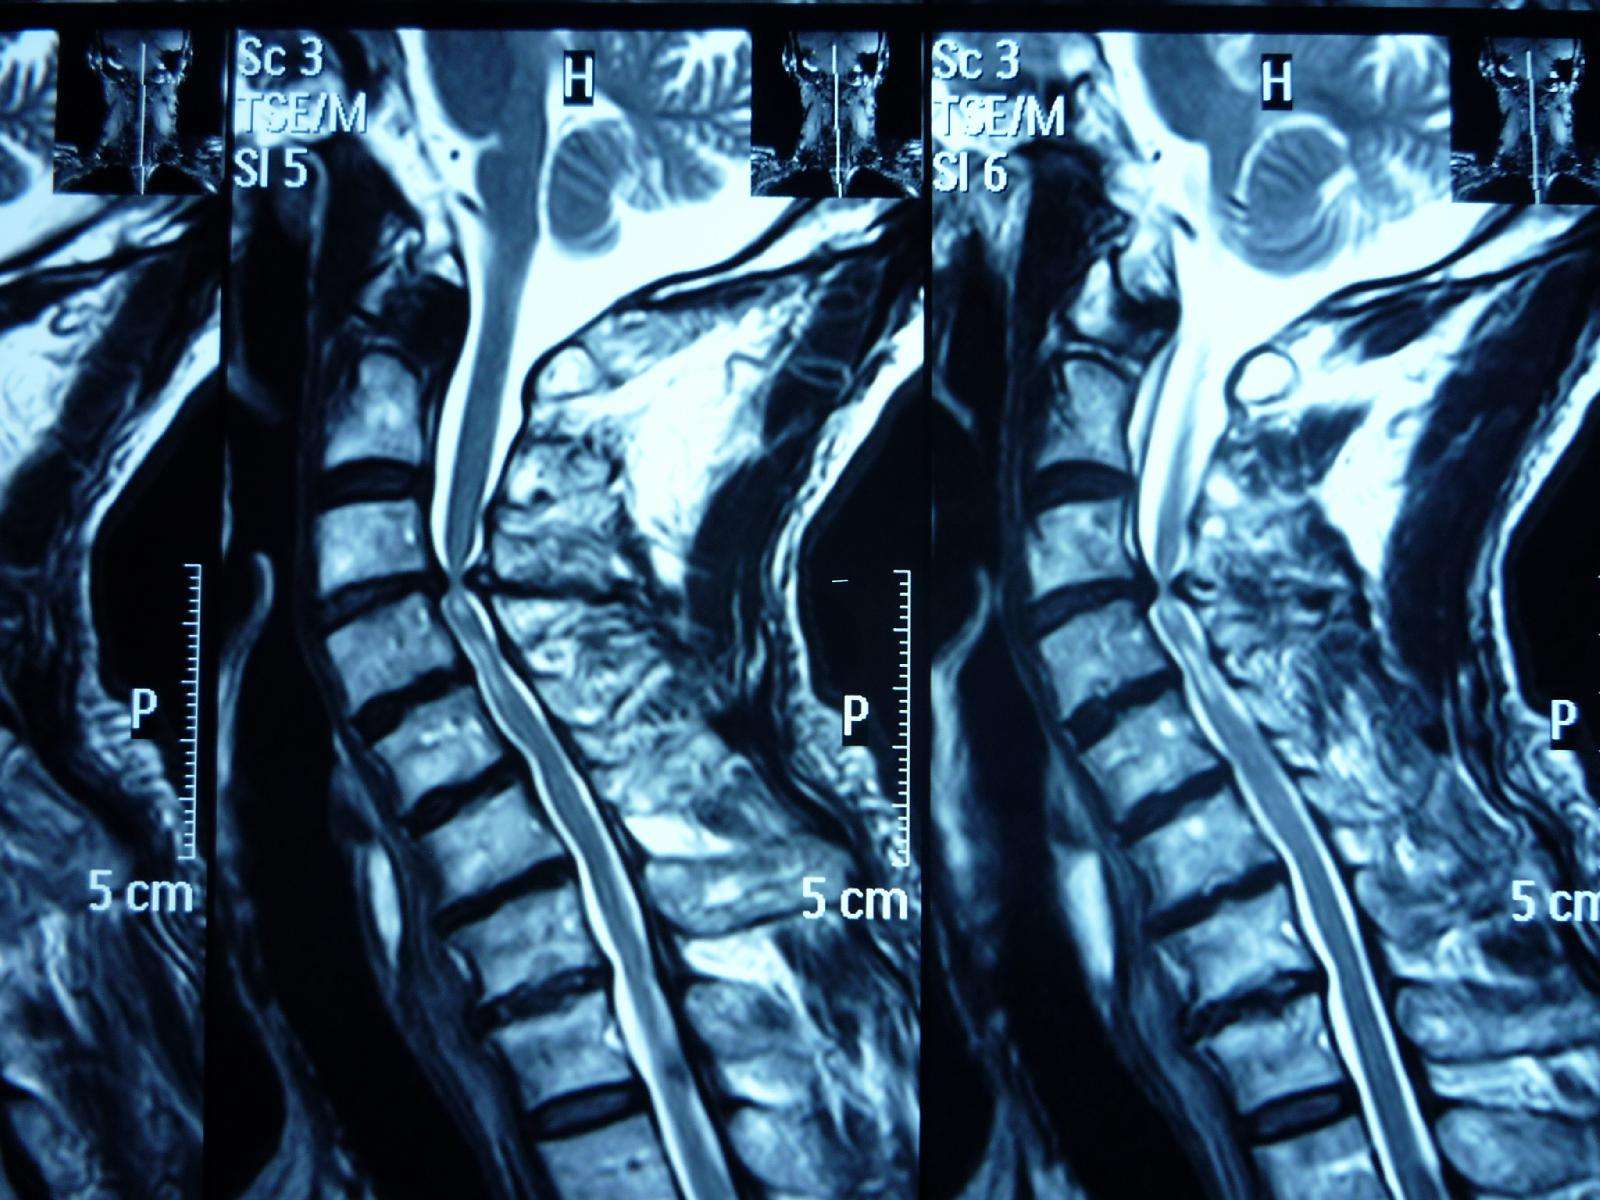

脊柱管狭窄症 Mri : 断面の脊柱管腔は純粋に客観的な評価となり,クモ膜 下腔の狭小化と術前の脊柱管狭窄症による症状の相関 表1 各椎間・撮影方法での脊柱管前後径比 l1/2椎間 l2/3椎間 l3/4椎間 腰椎mri 0.8660.830.679